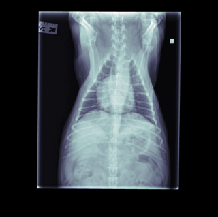

The data for this work consists of 390850 X-ray images, taken from 98660 veterinary sessions. These images were annotated by radiologists for over 41 diseases in a multi-label fashion, and are feedback from the usage of the RapidRead tool. Additionally, we have a dataset of 800 images with high-quality annotations, where the annotations were performed by 12 radiologists collaborating on each image. A sample of these X-ray images is shown in Figure 2.

This section presents visualizations of the Vision Transformer (ViT) attention maps. The ViT used is specific to lung diseases, and the attention maps are shown for patients with the positive label ’Pulmonary Mass’. The input to the ViT is a concatenated feature map, and the X-ray images have been mapped and displayed with the same concatenation and transformations applied to the augmented feature maps.

The attention maps show that the ViT focuses on the thorax region where the lungs are located, as expected. The results also demonstrate that the ViT remains focused on the thorax area even with different contexts in the X-ray images. This highlights the robustness of ViTs.